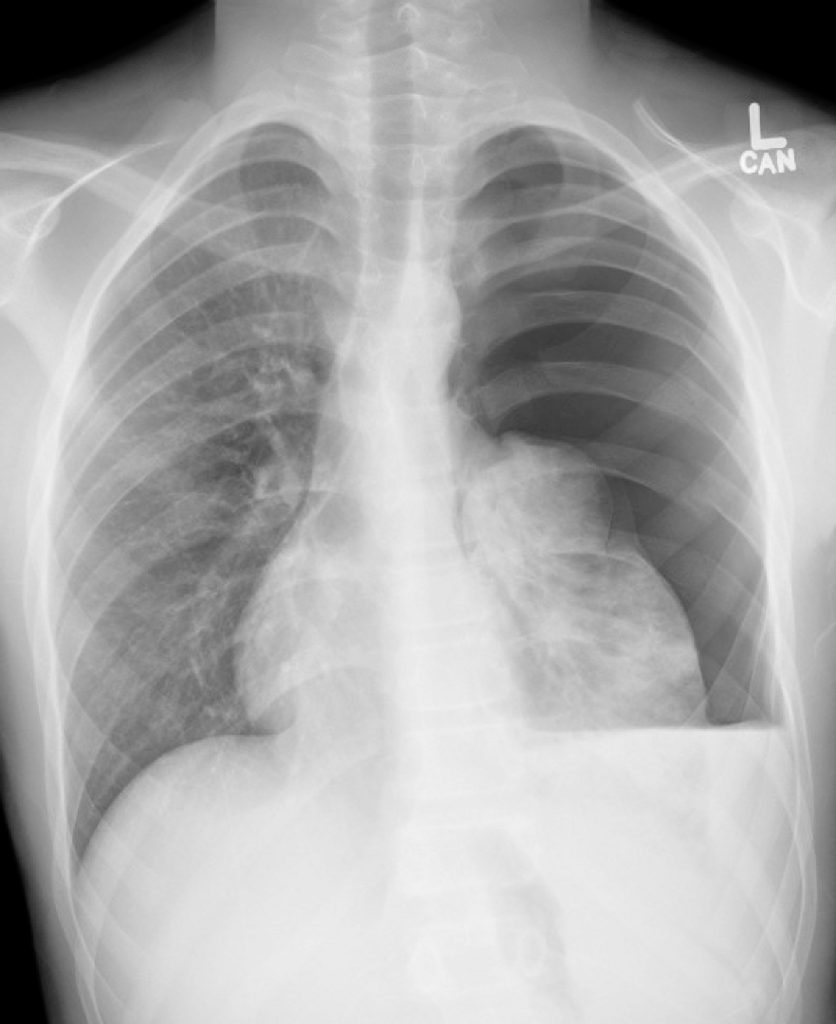

Case: A helmeted 13-yo-boy carrying a friend on his e-scooter ran into a pole and was pinned against the handle. He was brought in by his parents for chest pain from periphery to SMH. His CXR shows rib fractures and a tension hemopneumothorax. He is hypoxic and requires a decompression. What is the ideal location for needle decompression according to 2025 ATLS?